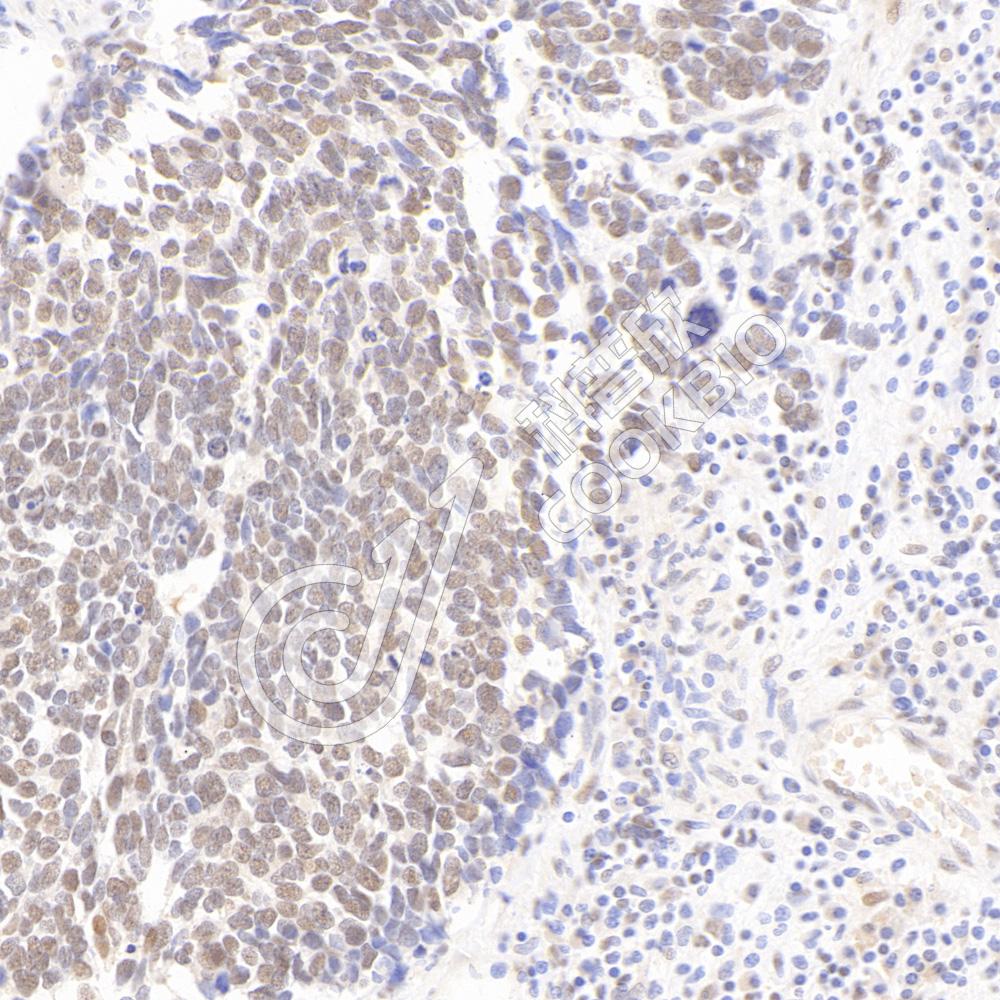

Glyceraldehyde 3-phosphate dehydrogenase (abbreviated as GAPDH or less commonly as G3PDH) is an enzyme of ~37kDa that catalyzes the sixth step of glycolysis and thus serves to break downglucose for energy and carbon molecules. In addition to this long established metabolic function, GAPDH has recently been implicated in several non-metabolic processes, including transcription activation, initiation of apoptosis, ER to Golgi vesicle shuttling, and fast axonal, or axoplasmic transport. In sperm, a testis-specific isoenzyme GAPDHS is expressed.